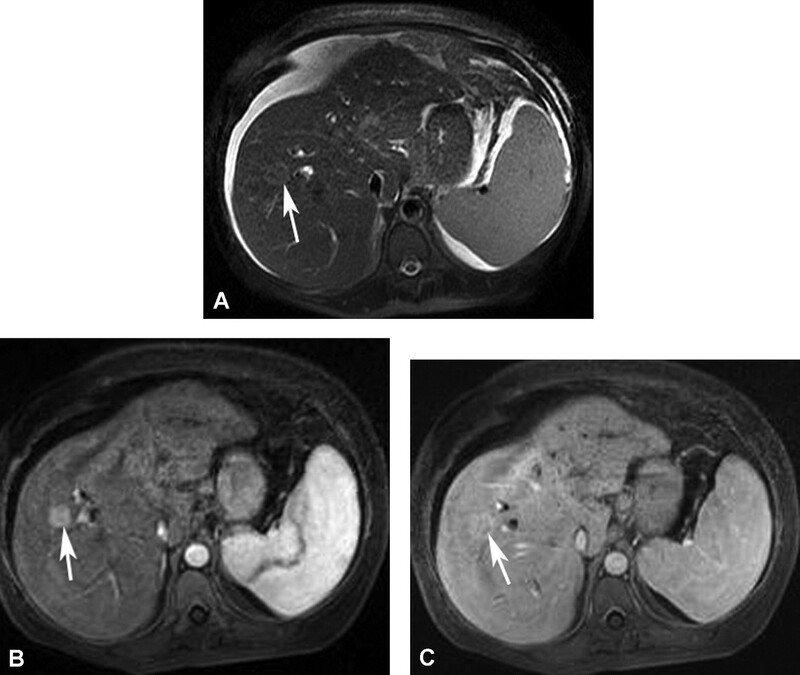

Hemangioma là u gan lành tính thường gặp nhất. Hemangioma thường gặp ở phụ nữ trẻ và 15-20% nhiều ổ. Mô học cho thấy một loạt các hồ máu và kênh mạch, các tổn thương lớn hơn tạo ra các vùng huyết khối và xơ. Siêu âm thấy một khối tăng âm, đồng nhất, giới hạn rõ, tăng âm phía sau yếu (Hình 1). Các tổn thương lớn hơn (>6cm) có thể không đồng nhất và giảm âm do huyết khối, hoại tử và thoái hóa nang. Các dấu hiệu CT cản quang gồm tăng quang dạng nốt ngoại vi ở thì động mạch với lấp đầy hướng tâm dần trong tổn thương ở thì tĩnh mạch cửa và thì muộn (hình 2). Vôi tĩnh mạch (phlebolith) có thể thấy trong tổn thương ở 15-20% trường hợp (Hình 2). MRI cho thấy tăng tín hiệu trung bình trên T2W, thường ít hơn so với nang đơn thuần, tín hiệu thấp trên T1W. MRI sau tiêm thuốc cho thấy bắt thuốc dạng nốt gián đoạn phía ngoại vi ở thì động mạch, đó là đặc điểm điển hình của hemangioma (Hình 3). MRI thì tĩnh mạch và thì muộn có thể thấy các nốt bắt thuốc lớn dần và hợp lưu với lấp dầy trung tâm ở các mức độ khác nhau tương tự như CT.

Hình 3. Hemangioma gan kinh điển. Tổn thương (mũi tên) tăng tín hiệu trên T2W FS single-shot fast spin-echo(SSFSE) (A). Có bắt thuốc dạng nốt ngoại vi (mũi tên) ở thì động mạch (B) và lấp dần vào trung tâm (mũi tên) ở thì tĩnh mạch cửa (C) và thì muộn (D) trên hình T1W 3D GRE.

Nói chung các tổn thương nhỏ hơn lấp đầy thuốc nhanh hơn các tổn thương lớn. Các hemangioma khổng lồ, thường lớn hơn 5-10cm, có thể không lấp đầy hoàn toàn thuốc tương phản (Hình 4 và 5), và có thể tạo ra các vùng nang giới hạn rõ ở trung tâm như dịc h đơn thuần. Các tổn thương nhỏ, <1cm, có thể lấp đầy nhanh và có thể không phân biệt được với HCC hoặc di căn giàu mạch máu. Tuy nhiên, u giàu mạch máu thải thuốc nhanh, trong khi hemangioma tăng quang dai dẳng do thải thuốc chậm. Ngoài ra hemangioma còn có tín hiệu cao trên T2W với thời gian echo lớn hơn 112ms, trong khi các u ác tính không thấy tín hiệu cao. Hình ảnh thì động mạch với thời gian tối ưu cung cấp thông tin chẩn đoán quan trọng nhất để xác định đặc điểm hemangioma.